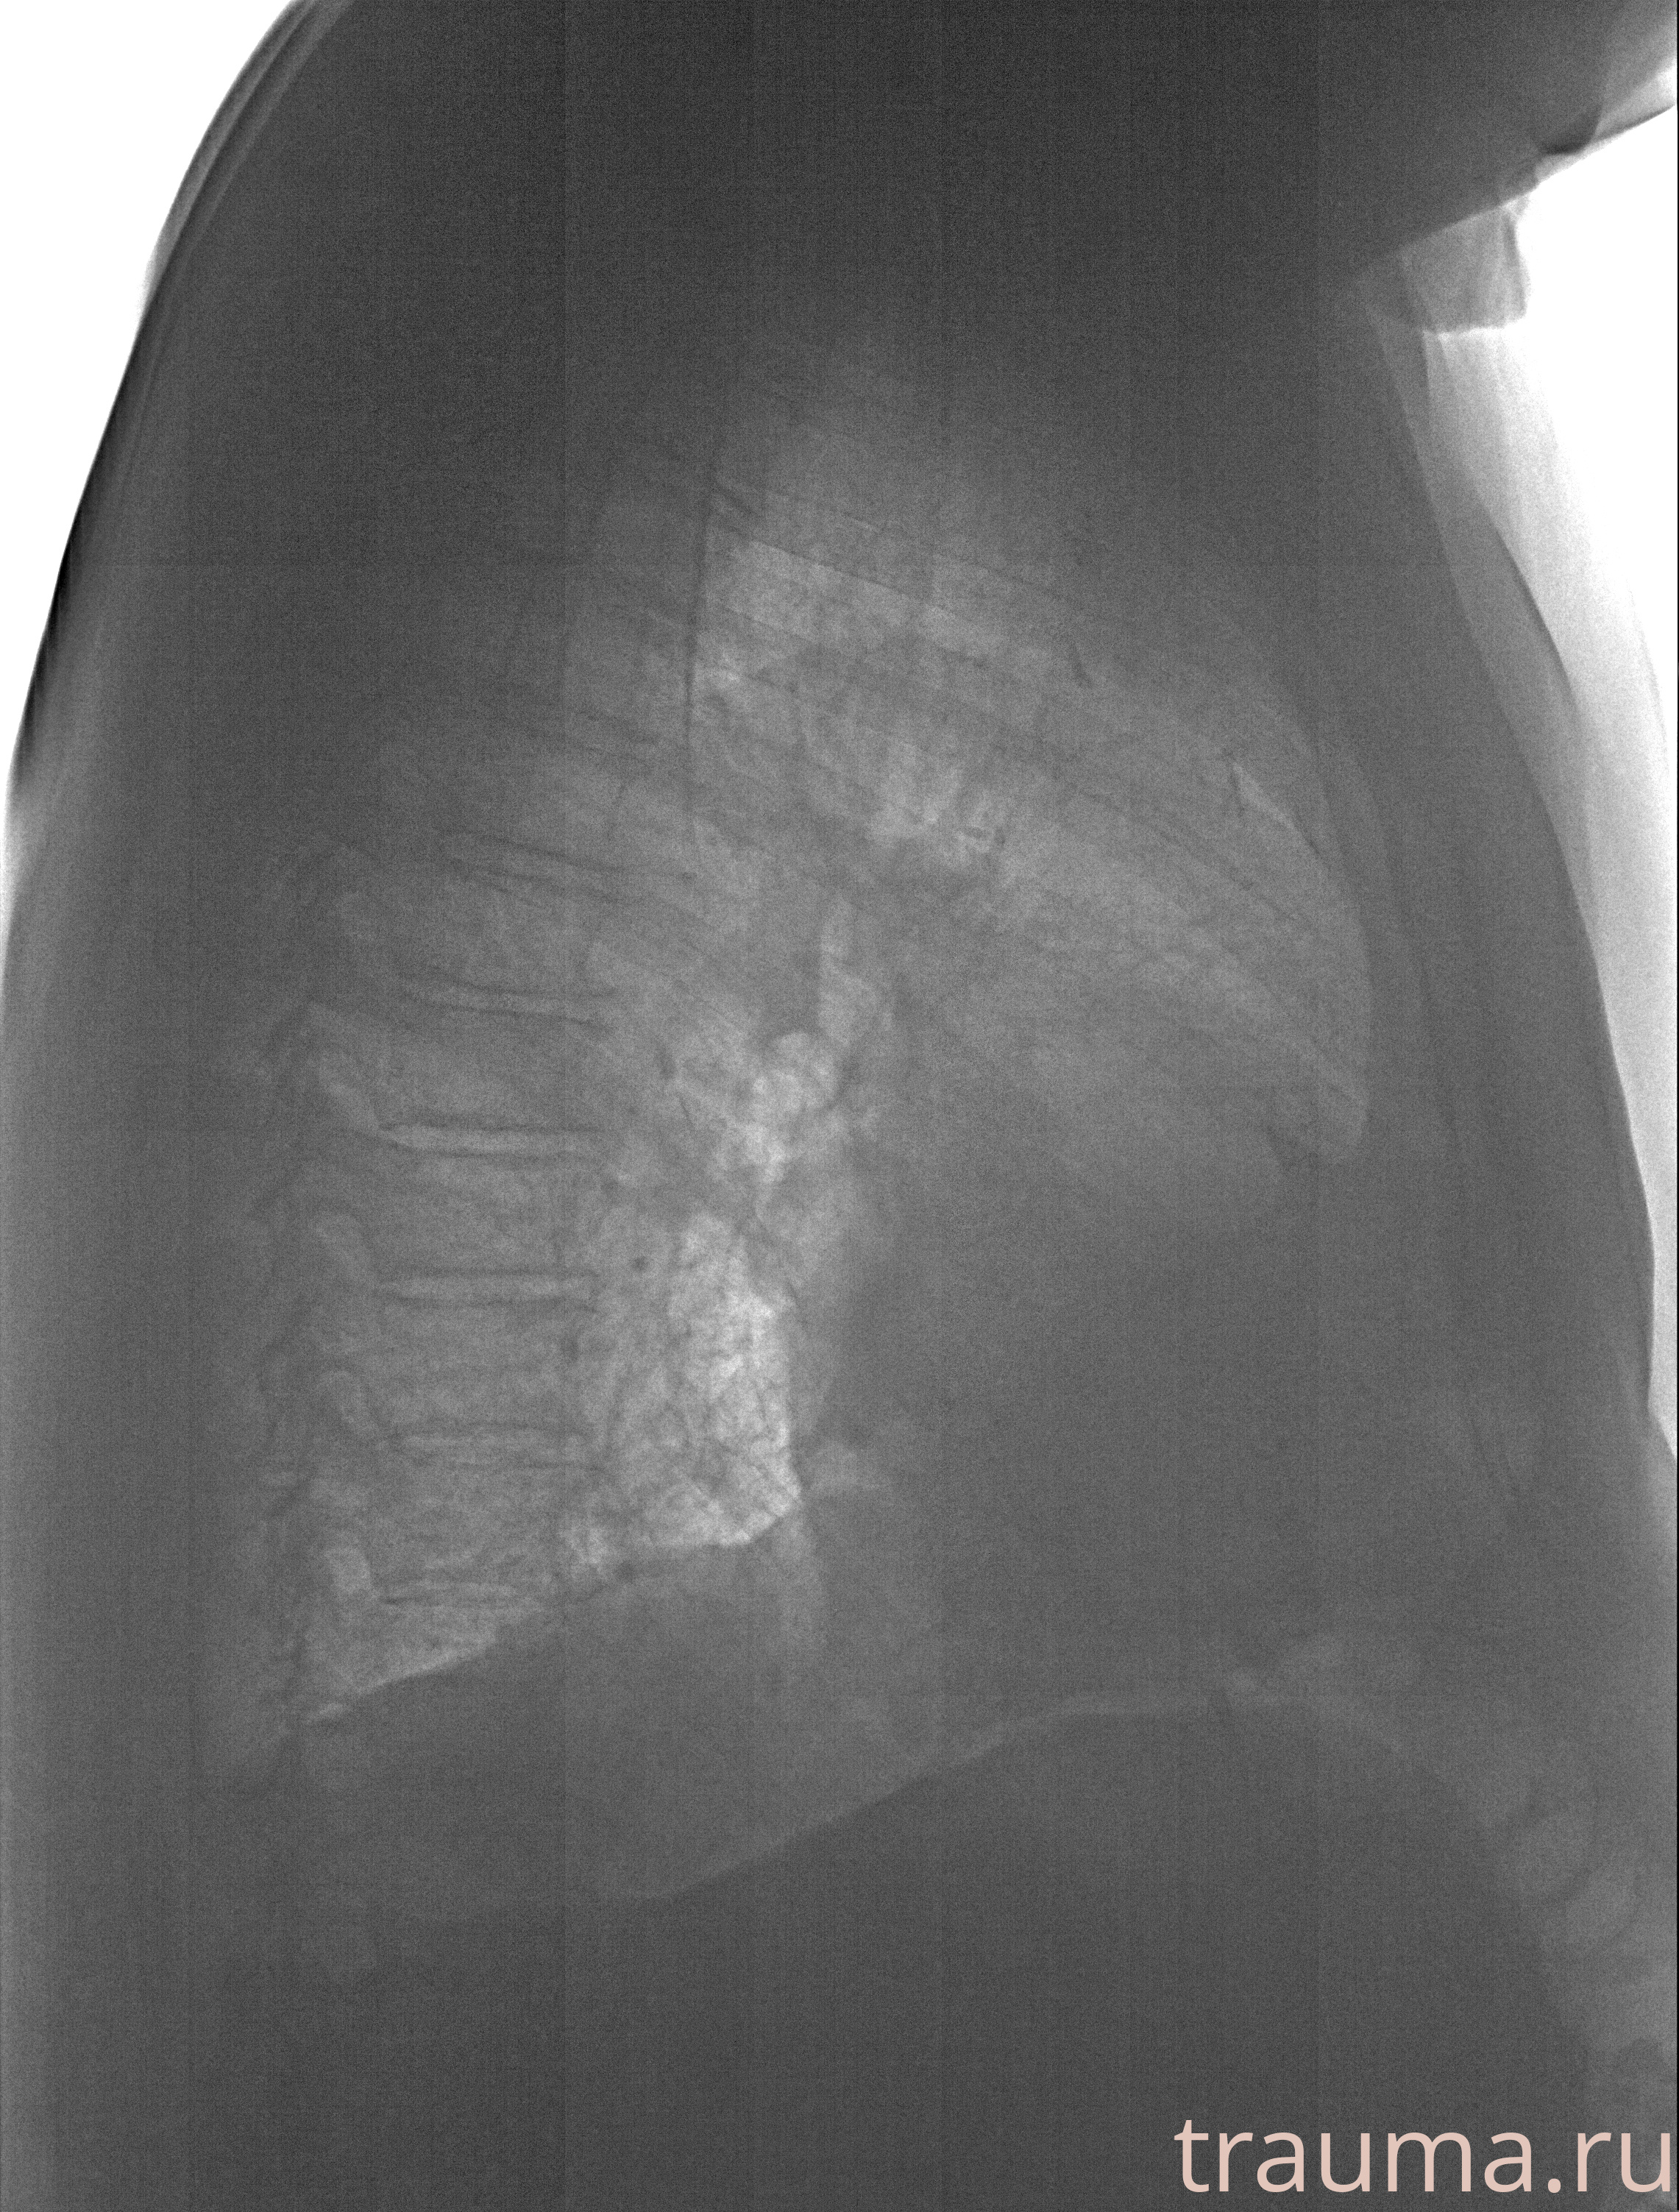

Рентгенограммы

Рентген на дому: по вашему адресу приезжает врач-рентгенолог, травматолог-ортопед с мобильным рентгеновским аппаратом, проводит диагностику травмы или заболевания, делает необходимые рентгенограммы, дает рекомендации по дальнейшему лечению. Получить качественные снимки в домашних условиях возможно благодаря уникальной методике, разработанной МосРентген Центром для института  Склифосовского

при переломе шейки бедра и пневмонии от компании МосРентген Центр - партнера Института имени Склифосовского